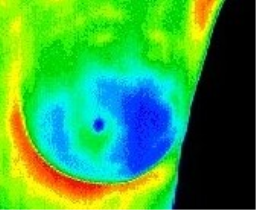

MG.DIGITAL is a public benefit company established in 2019 with the aim of providing imaging services without ionizing radiation to all women at reasonable prices using advanced thermographic equipment and digital ultrasound.